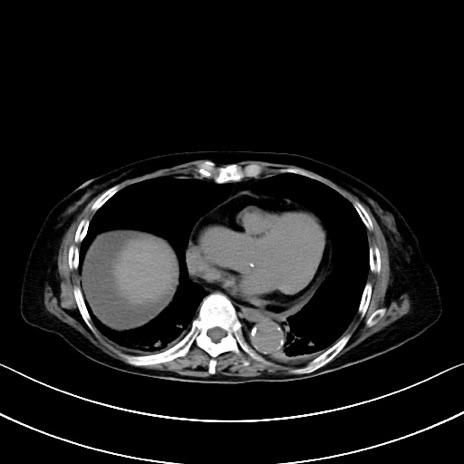

症例40(横断像)他院1日前

横断像

他院CT